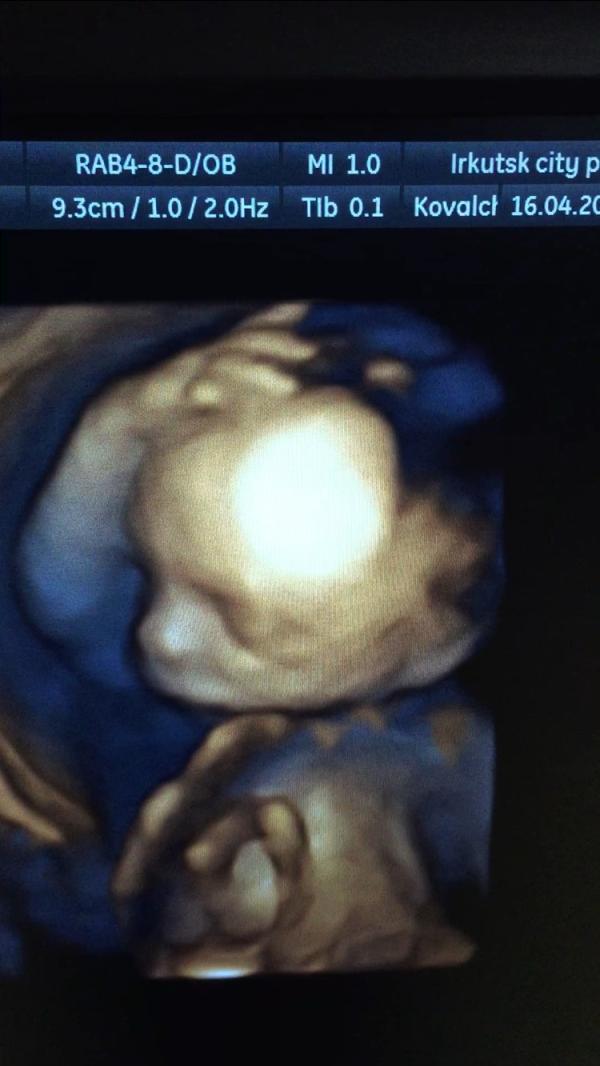

Вчера была на ктг - дочь спит. И последние две недели она спит регулярно. Я крайне редко ощущаю пиночки, только периодически ногу вытягивает во сне. Это вообще нормально?

@onti_ponti все показатели всю беременность в норме, скрининги, анализы, ктг...Но я переживаю, что не пинается(

И как результаты ктг ? В норму уложились ? Если переживаете , сходите на доплер

@zheglenok89 я кстати вчера тоже на ктг была и у меня из 8, семь показателей только норм и назначили актовегин